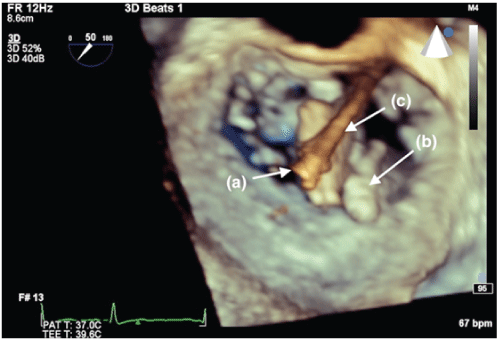

图1:食管中部腔体视图(放大)显示连叶A2段和严重的后向MR射流(a)。LA =左心房;PL =二尖瓣后叶;A2 =二尖瓣前叶A2段;MR =严重二尖瓣反流。